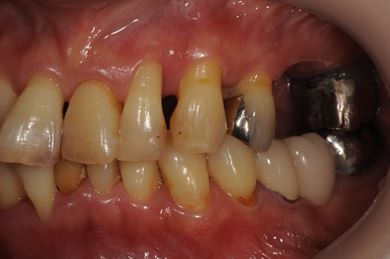

| 性別/年齢 | 女性 / 51歳 | ||||||||||||||||||||||||||||||||

| 主訴 | 他の歯科医院で入れ歯を入れたが、滑舌や味などで不自由を感じている。インプラントは難しいと言われたが、可能かどうかみていただきたい。 | ||||||||||||||||||||||||||||||||

| 治療方針 | サイナスリフトにより上顎洞を拳上し、インプラント治療を可能にする。 | ||||||||||||||||||||||||||||||||

| 治療内容 | インプラント3本(サイナスリフト)、ハイブリッドセラミッククラウン5本 | ||||||||||||||||||||||||||||||||